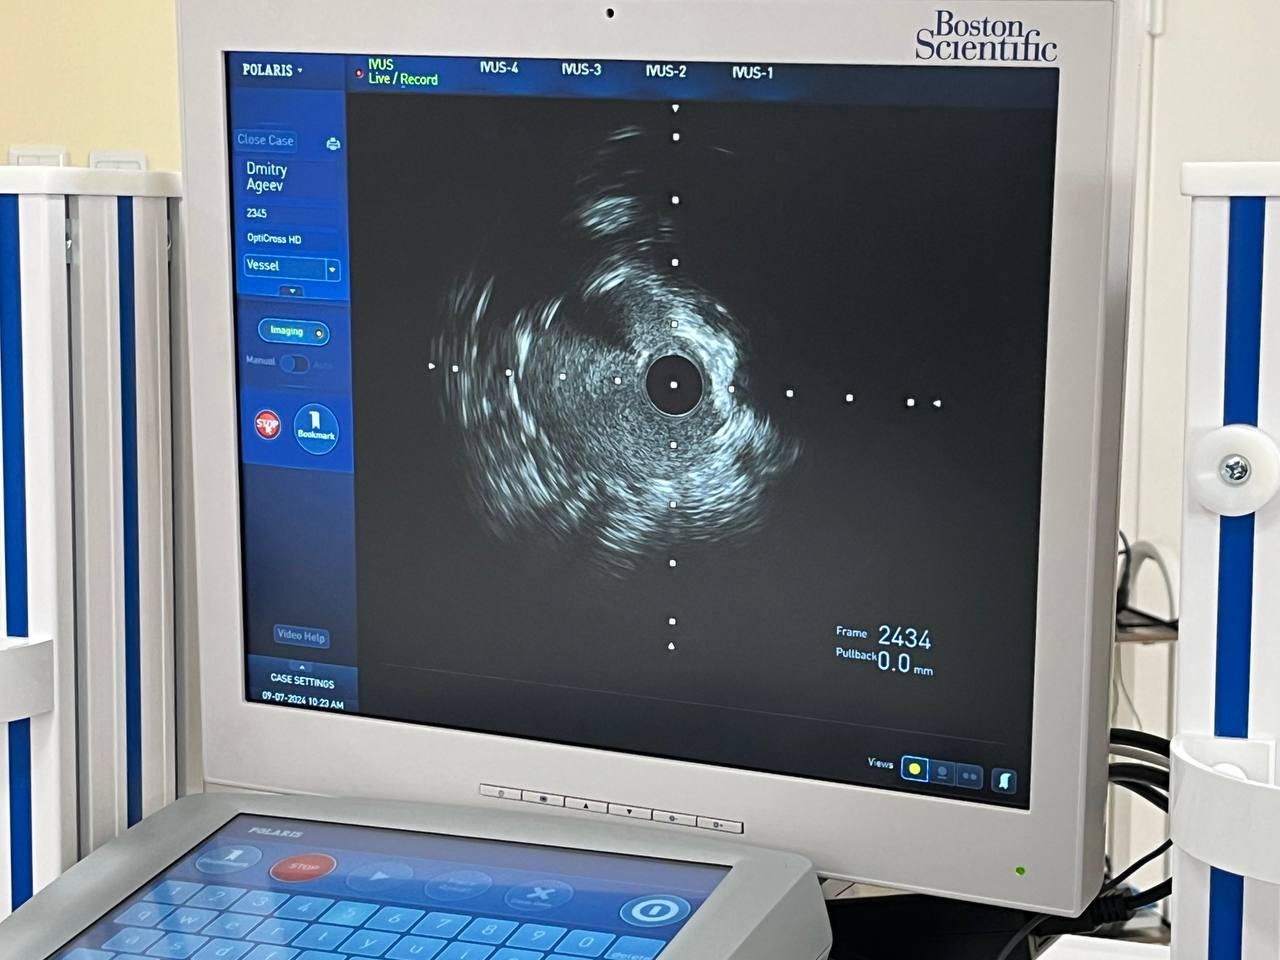

Методику внутрисосудистого ультразвукового исследования артерий сердца заводят в свою практику специалисты регионального сосудистого центра Клинической больницы № 6 имени Г. А. Захарьина. Технология призвана помочь врачам, борющимся за жизнь пациентов.

«Работа нашего регионального сосудистого центра постоянно  совершенствуется. Благодаря тесному сотрудничеству с коллегами из других регионов и стран мы работаем над внедрением высокотехнологичных методов лечения сердечно-сосудистых патологий в повседневную практику, - говорит заведующий региональным сосудистым центром Клинической больницы № 6 имени Г.А. Захарьина Дмитрий Максимов. - В частности сейчас к нам на длительную апробацию поступила консоль по внутрисосудистой визуализации коронарных артерий. Это новейшее оборудование, которым в нашем субъекте не пользовался никто».

ВСУЗИ – самый современный на сегодняшний день высокотехнологический метод внутрисосудистой визуализации коронарных артерий. Проводится путем заведения в коронарную артерию ультразвукового датчика диаметром всего 1 мм. В ходе вмешательства можно определить степень сужения и протяженность поражения коронарной артерии, а также оценить морфологию атеросклеротической бляшки.

По словам Дмитрий Борисовича, внедрение внутрисосудистой визуализации коронарных артерий — большой шаг вперёд для кардиологической службы нашего лечебного учреждения.

«Мы уже применили данную методику, что, безусловно, позволит повысить эффективность проводимых вмешательств», — отмечает руководитель РСЦ больницы Захарьина.

Разрешающая способность оборудования настолько высока, что обеспечит лучший контроль во время процедуры для достижения оптимального результата и минимизации осложнений.